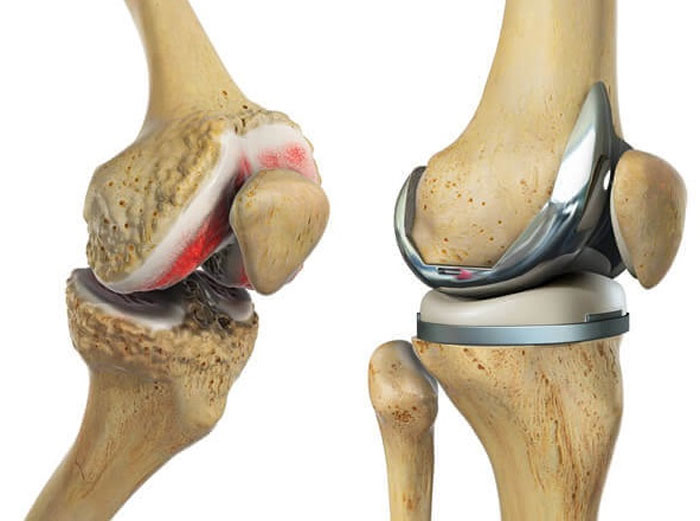

Эндопротезирование сустава – это полная замена поврежденного сустава искусственным протезом. Оно показано при выраженном, распространенном остеоартрозе с тотальным разрушением суставных поверхностей, когда другие методы лечения неэффективны, а боль значительно ограничивает качество жизни. ЭПС чаще рекомендуется пациентам старшего возраста. Преимуществами эндопротезирования являются быстрое и предсказуемое избавление от боли, более короткий период восстановления до полной нагрузки и высокая вероятность достижения стабильного функционального результата. Недостатки включают необходимость использования искусственного материала, риск износа протеза с течением времени и возможность специфических осложнений, связанных с имплантатом.

| Основная цель | Сохранение собственного сустава, перераспределение нагрузки, отсрочка протезирования. | Полная замена поврежденного сустава искусственным имплантатом. |

| Долгосрочный результат | Отсрочка протезирования на 10-15+ лет, сохранение естественных тканей. | Предсказуемое устранение боли, высокая функциональность, срок службы протеза 15-20+ лет. |